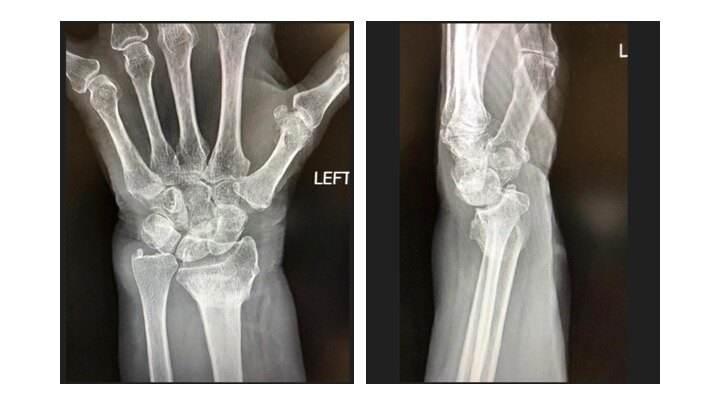

通过上述骨折修复的过程我们看到,骨折仅会让骨骼出现骨痂,但骨痂最终仍会消失,所以骨折并不能提升骨患者的骨强度。而且,很多人骨折之后还会出现各种后遗症,较为常见的就是骨折不愈合或愈合缓慢、畸形愈合。

但也有部分患者在骨折愈合之后,会产生运动能力下降、活动受限的症状;还有一小部分患者在骨折痊愈之后,受凉、潮湿时,患处仍会出现疼痛的症状。所以,骨折恢复后并不会提升骨骼的强度,还可能会有后遗症。